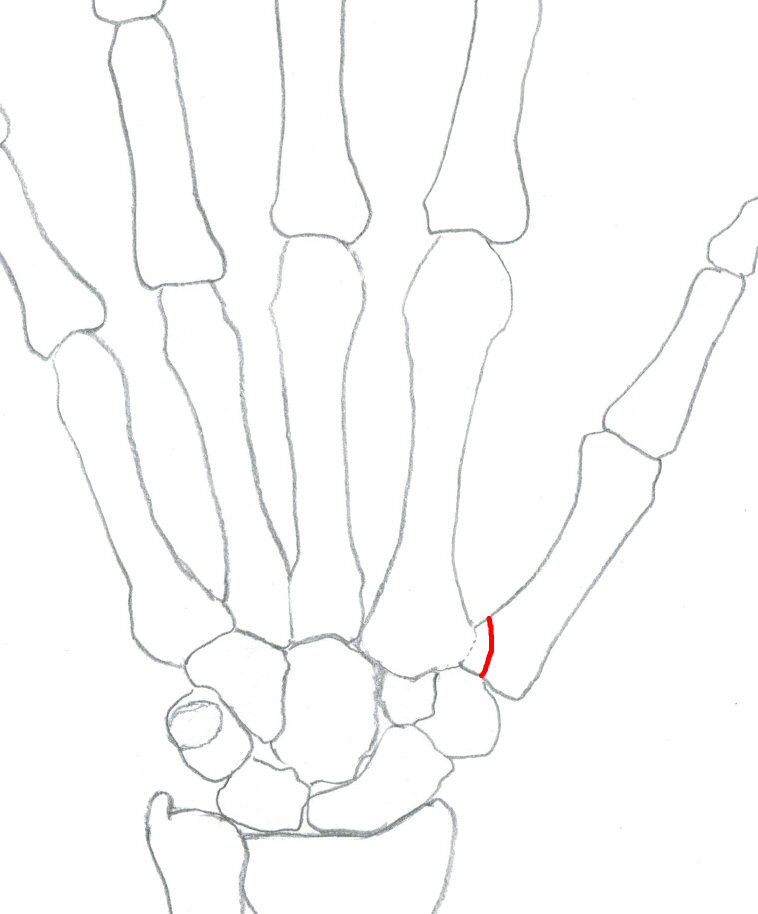

Tenneb-fraktur = omvänd bennettfraktur: intraartikulär fraktur i basen av metakarpale 5, volart-radialt fragment ligger på plats medan ECU-senan (extensor carpi ulnaris) drar distala fragmentet ulnart-proximalt.